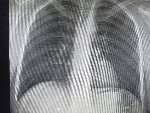

Здравствуй двачик, пишет вам простой рентгенолог из мухосранской поликлиники, сегодня я буду флексить зарплатой за ноябрь! Аж ПЯТЬДЕСЯТ ТРИ ТЫЩИ ПЕРЕВЕДУТ! С пруфом! А чего достигли вы? Ну и в доктора тож поиграем! Я буду вам картинки показывать, а вы пиздецомы находить! Найдите пиздецому на фтчк! Отчет еще по фог считать квартальный и годовой сегодня :-(